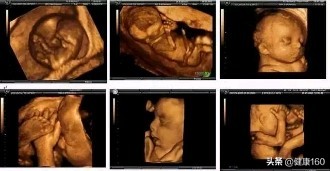

普通B超和彩色B超看到的都只是一个平面,而三维和四维B超看到的是胎儿的立体图像。而三维和四维的区别呢?仅仅就在于一个“时间维”。通俗的来说,三维就好比是图片,而四维就好比是录像。三维是静态的,而四维却是动态的,可以看到宝宝一连串的动作。

说得更直白一点,如果将你的家用电脑中装上类似软件,你就可以把普通B超的图像自己在家里转换成立体的了。在诊断的意义上,三维、四维没有任何对诊断更有利的地方,只不过是不懂得B超图像的人也能看出模样而已。它的意义也就在于,您能看见宝宝在肚子里的立体模样了。